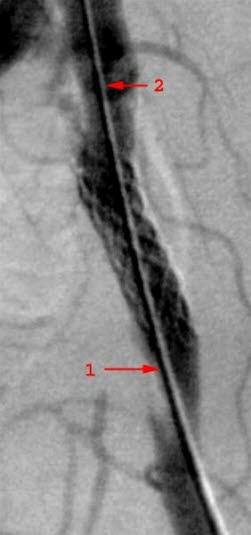

Zwężenie w tętnicy biodrowej, zdjęcie rentgenowskie w trakcie angiografii

Zwężenie w tętnicy biodrowej leczone stentem, zdjęcie rentgenowskie w trakcie angiografii